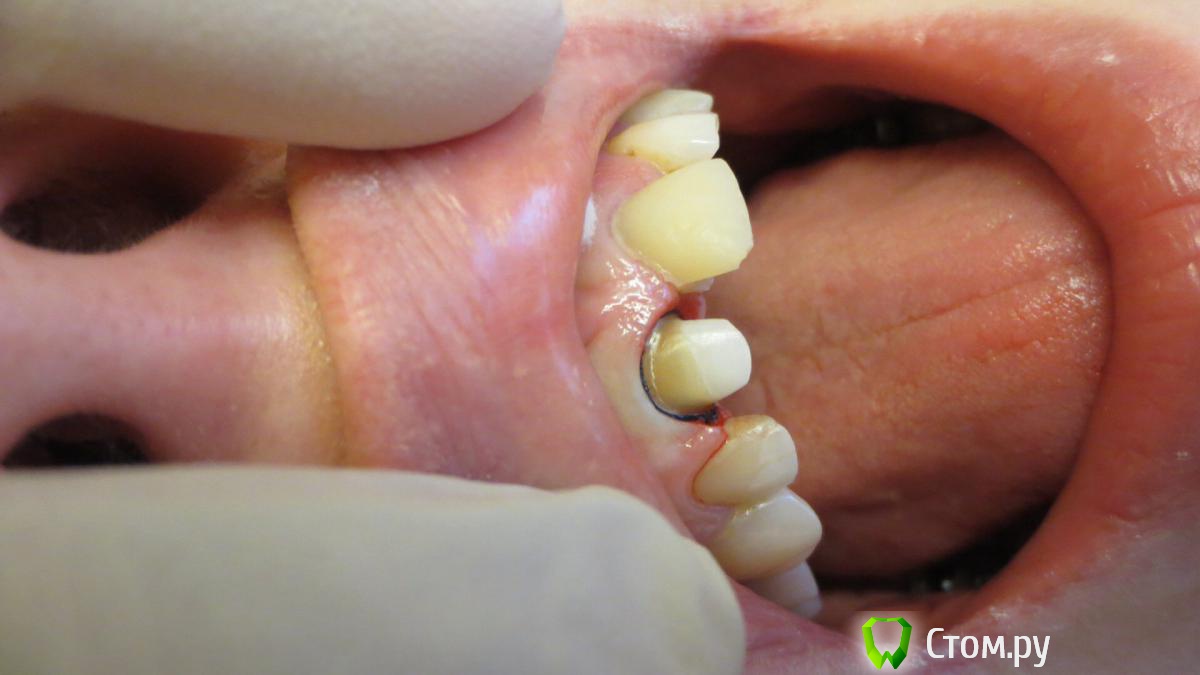

Военный Врач Опубликовано 28 февраля, 2014 Поделиться Опубликовано 28 февраля, 2014 (изменено) С позволения ТС-посмотрите коллеги и мой преп чтоб тему отдельно плодить Изменено 28 февраля, 2014 пользователем Военный Врач Ссылка на комментарий

chervoncevdaniil Опубликовано 2 марта, 2014 Поделиться Опубликовано 2 марта, 2014 С позволения ТС-посмотрите коллеги и мой преп чтоб тему отдельно плодитьПо-моему очень аккуратный преп,вы с нитью препарируете или перед оттиском ставите только? Ссылка на комментарий

oleg07 Опубликовано 3 марта, 2014 Поделиться Опубликовано 3 марта, 2014 очень красивый преп))) Ссылка на комментарий

Evikrol Опубликовано 3 марта, 2014 Автор Поделиться Опубликовано 3 марта, 2014 С позволения ТС-посмотрите коллеги и мой преп чтоб тему отдельно плодитьА не глубоко уступ? Это циркониевая вкладка? Если да то и циркониевая коронка планируется? Если так то зачем погружать уступ под десну? Ссылка на комментарий

k.t.m. Опубликовано 3 марта, 2014 Поделиться Опубликовано 3 марта, 2014 если под безметалл то как то перепреп,ладно тут зуб депульпированный, сепарация проведена так что срезан 1.2 Ссылка на комментарий

Военный Врач Опубликовано 5 марта, 2014 Поделиться Опубликовано 5 марта, 2014 А не глубоко уступ? Это циркониевая вкладка? Если да то и циркониевая коронка планируется? Если так то зачем погружать уступ под десну?Вкладка cosmopost Ссылка на комментарий